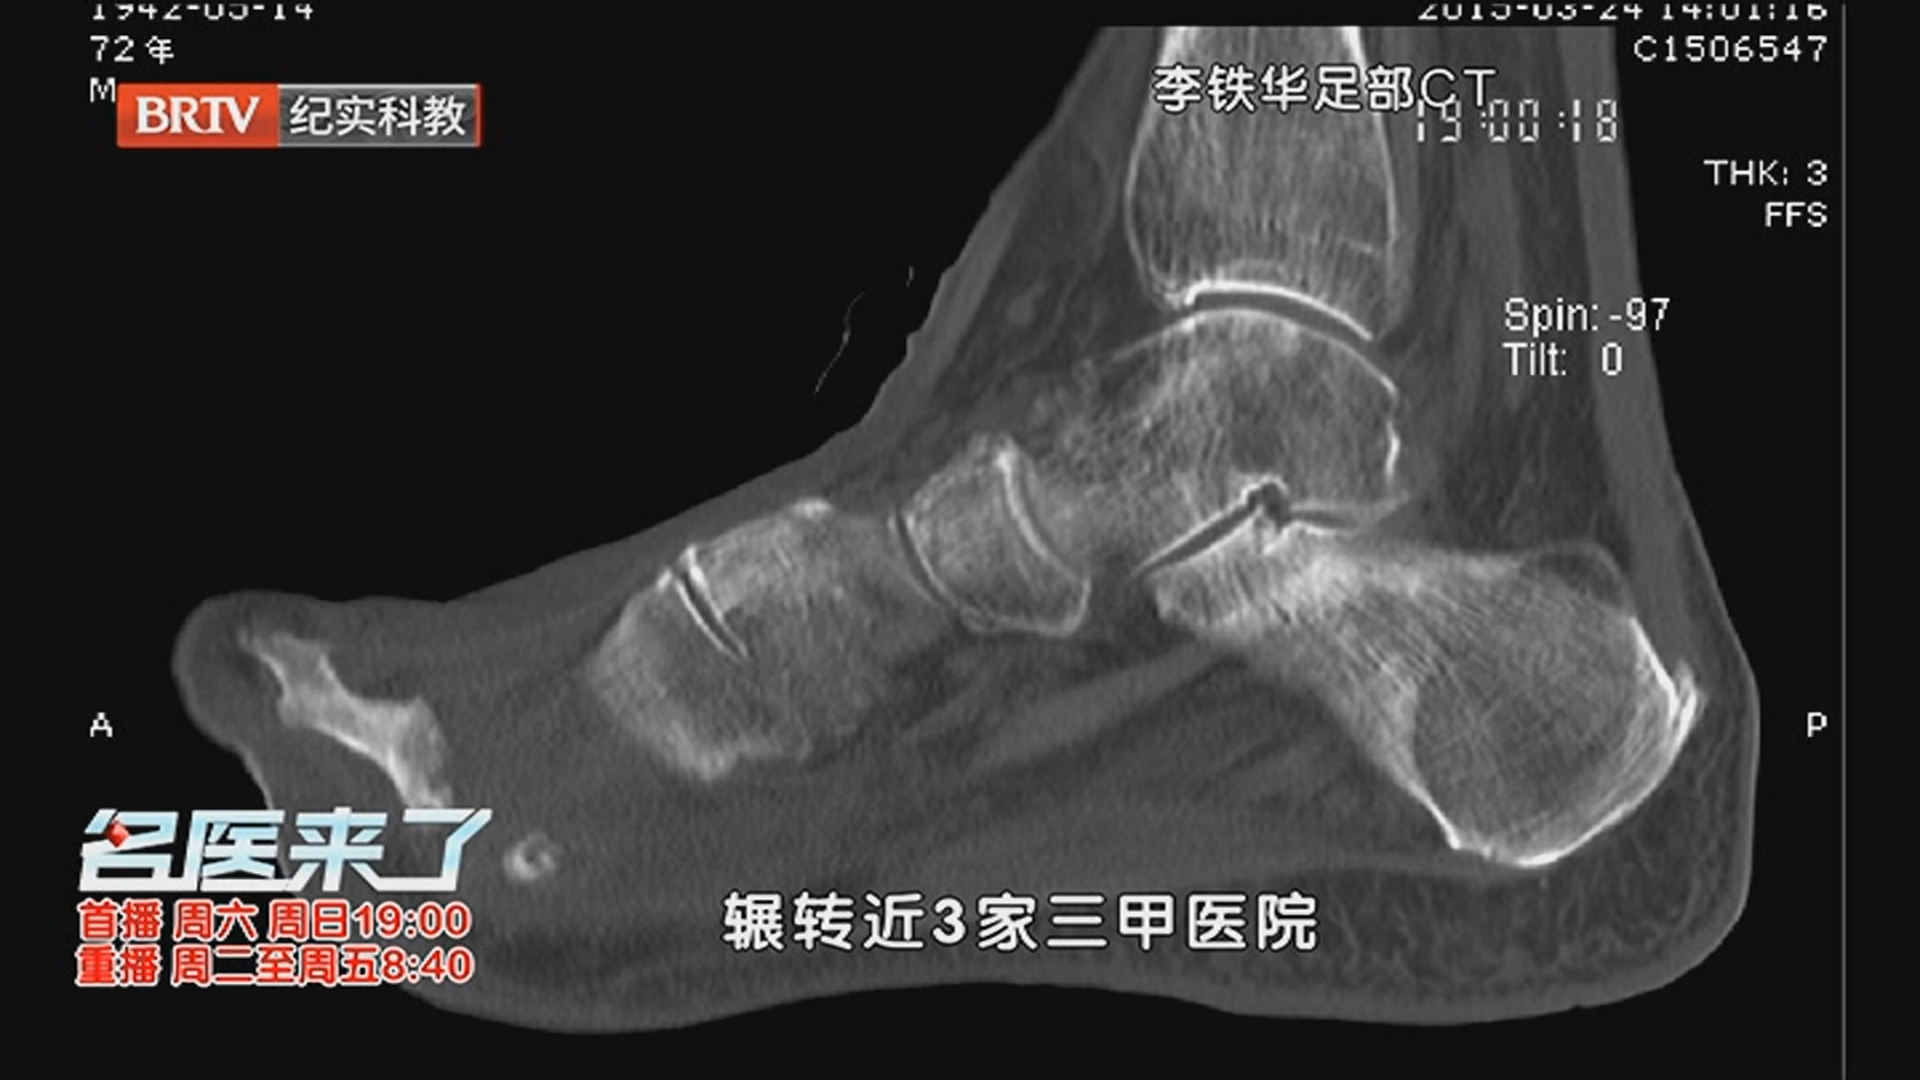

《名医来了》20251122中西医携手护糖足_北京时间